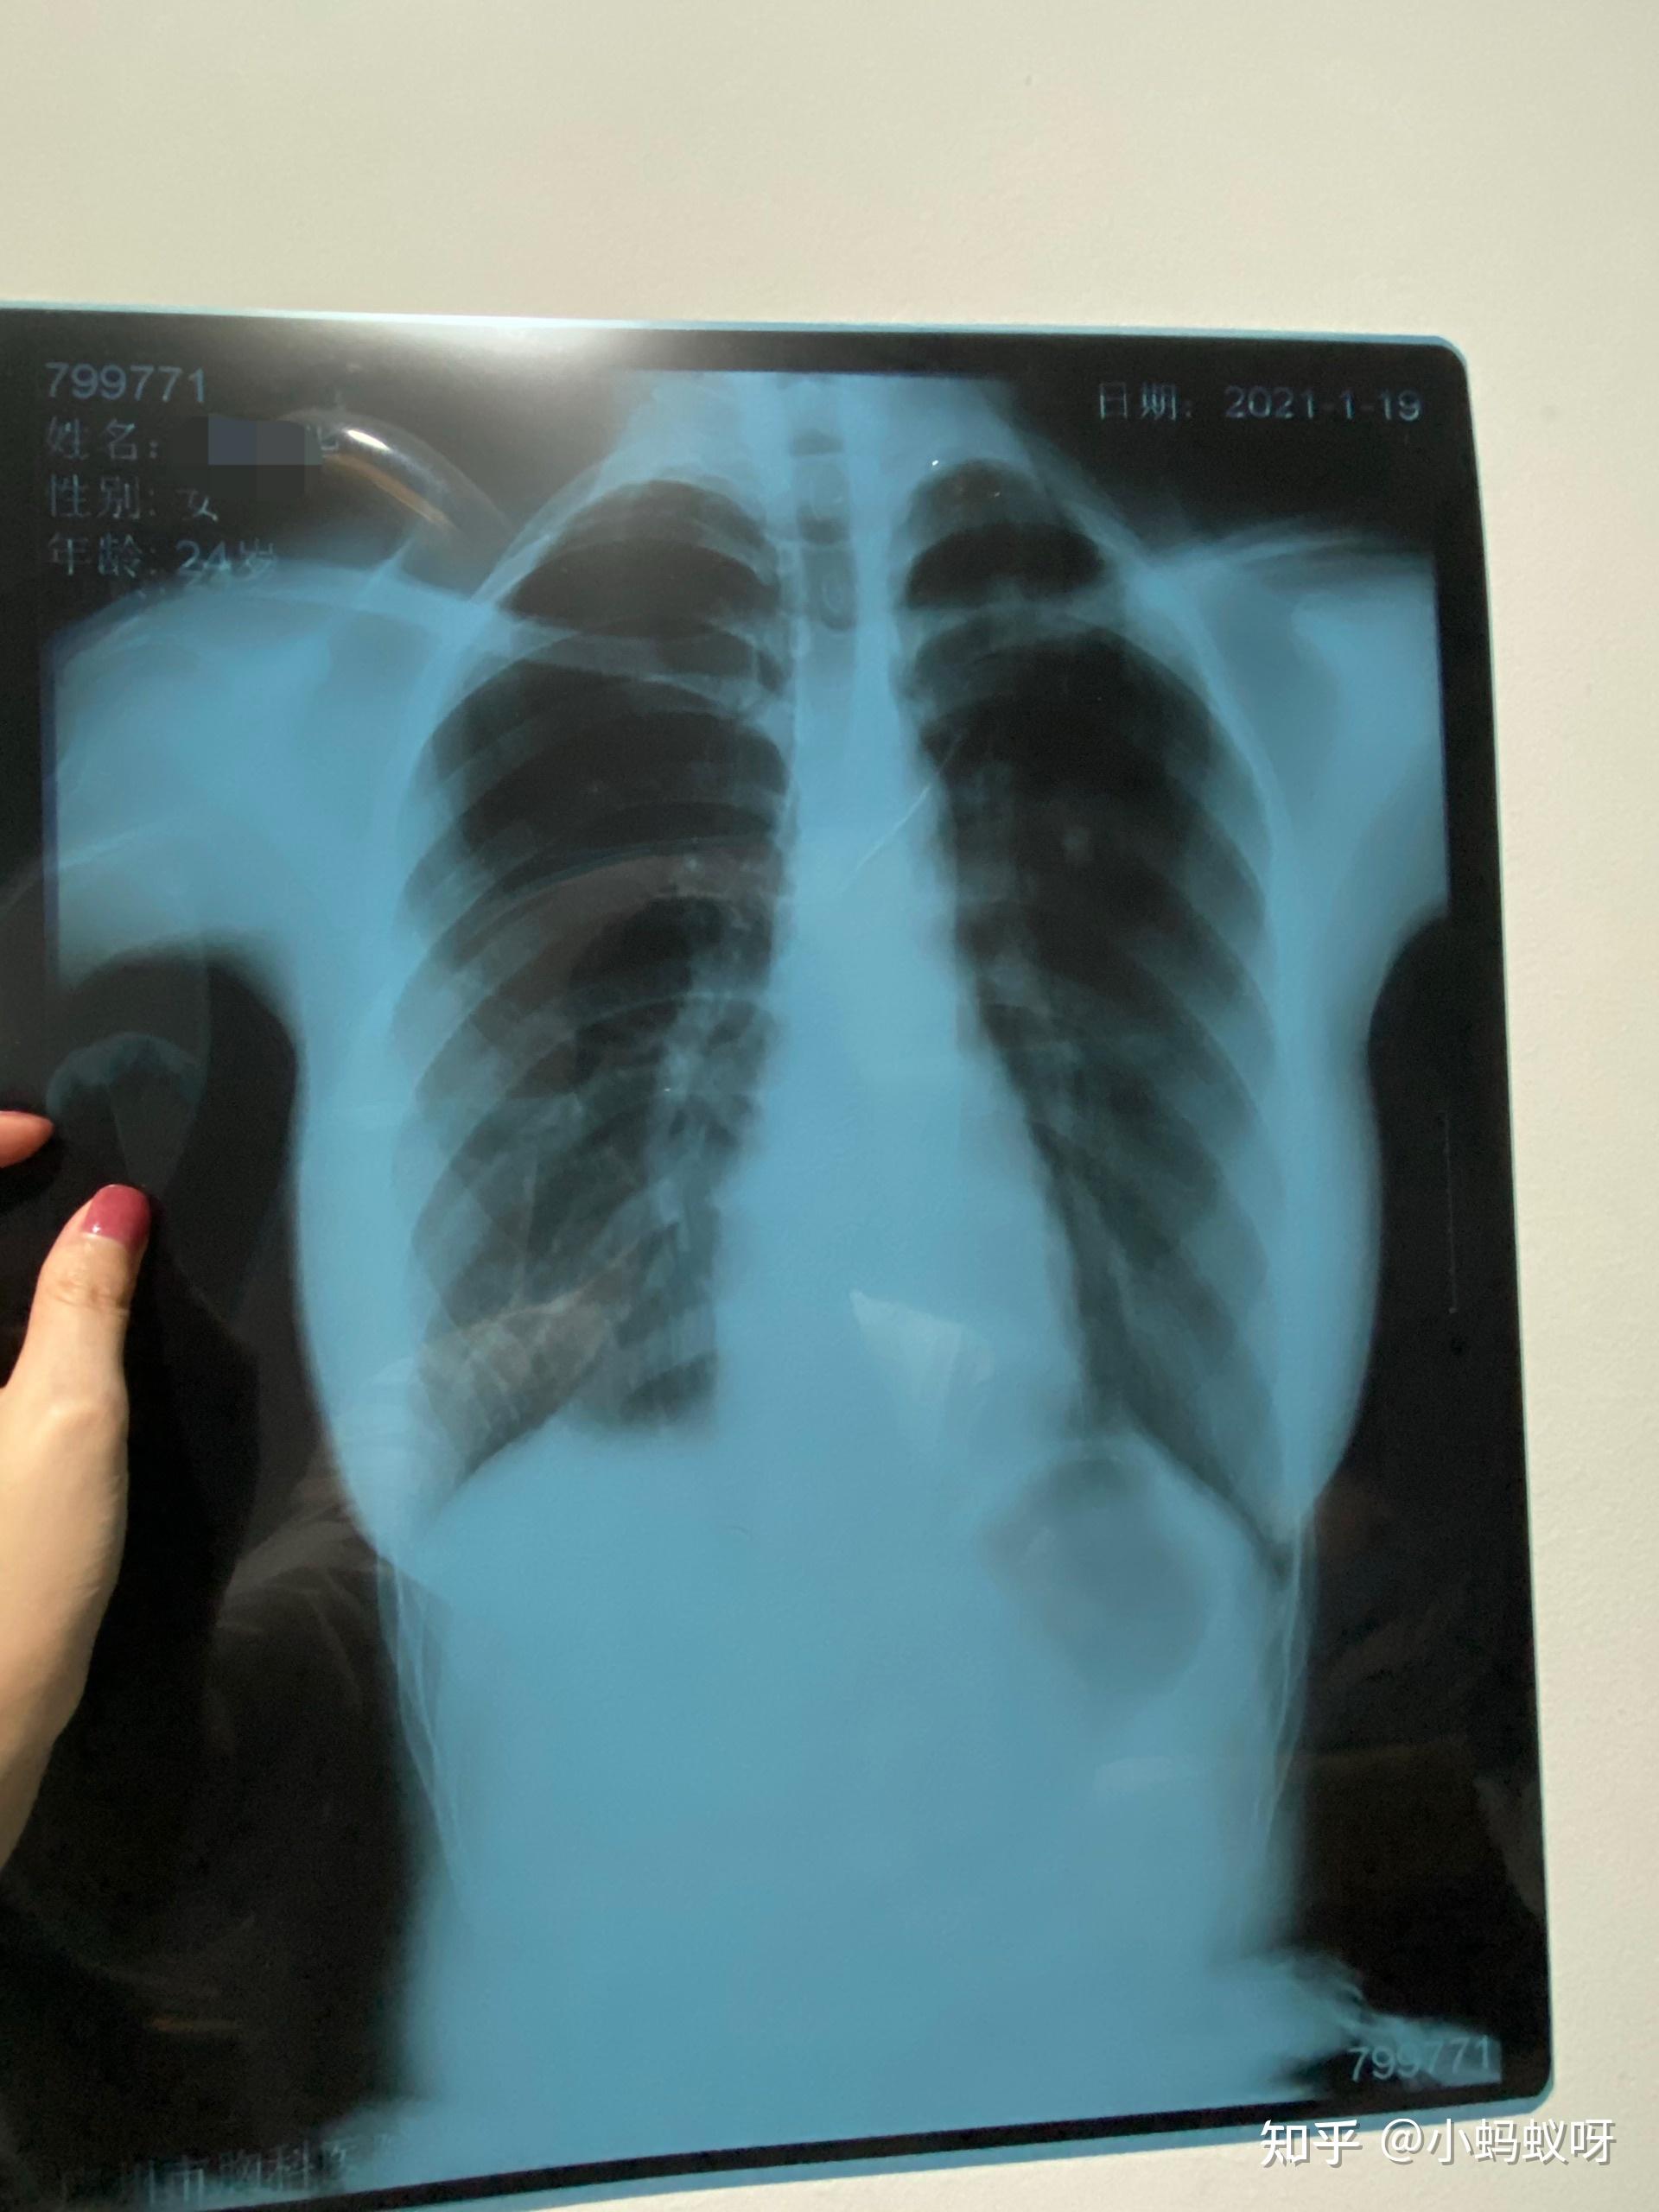

肺结核拍片,肺结核胸片

我的抗结核之路